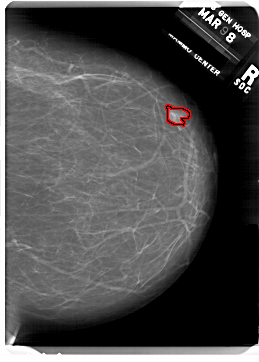

A_1815_1.RIGHT_CC

RIGHT_CC LINES 6871 PIXELS_PER_LINE 4921 BITS_PER_PIXEL 12 RESOLUTION 43.5 OVERLAY

FILE: A_1815_1.RIGHT_CC.OVERLAY

TOTAL_ABNORMALITIES 1

ABNORMALITY 1

LESION_TYPE MASS SHAPE TUBULAR MARGINS CIRCUMSCRIBED

ASSESSMENT 4

SUBTLETY 4

PATHOLOGY BENIGN

TOTAL_OUTLINES 1

BOUNDARY